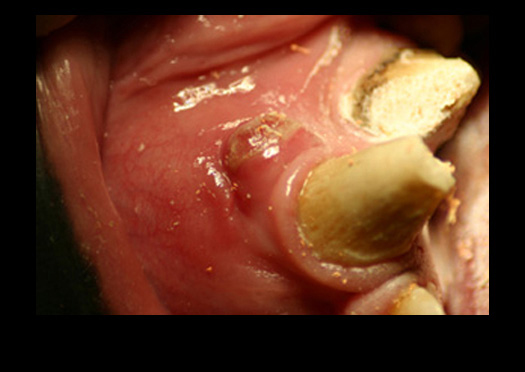

Banner Images and Descriptions